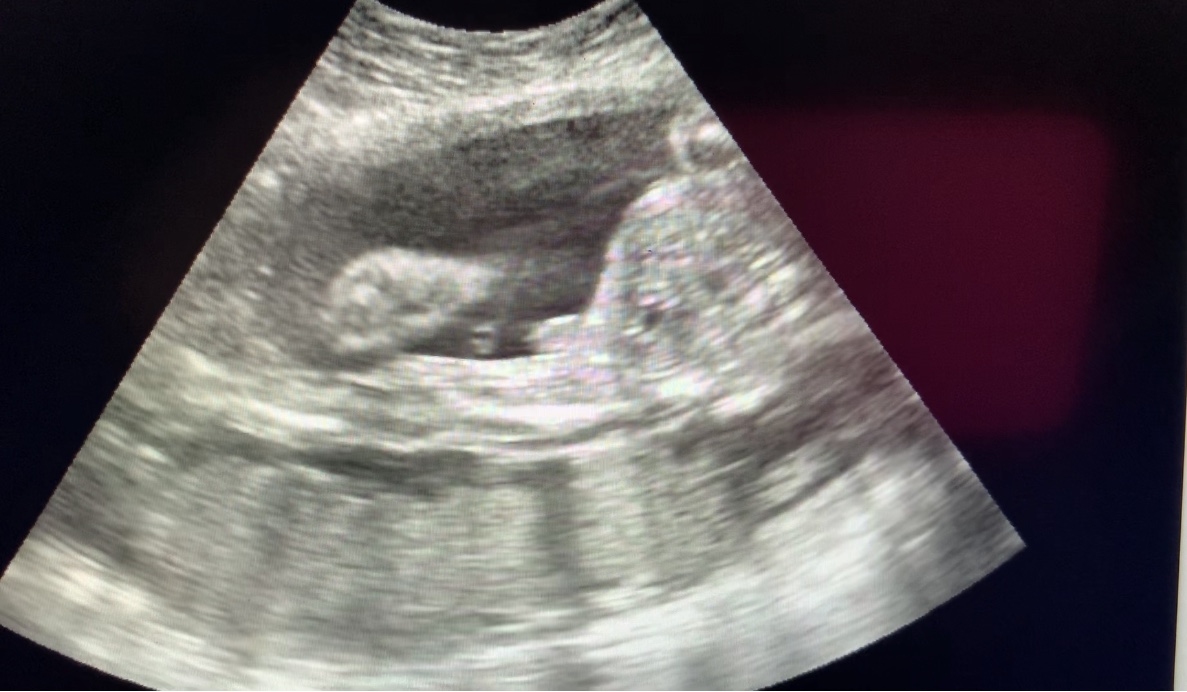

Attachment 42456 Here’s another ultrasound from a different prospective.. Boy or girl?